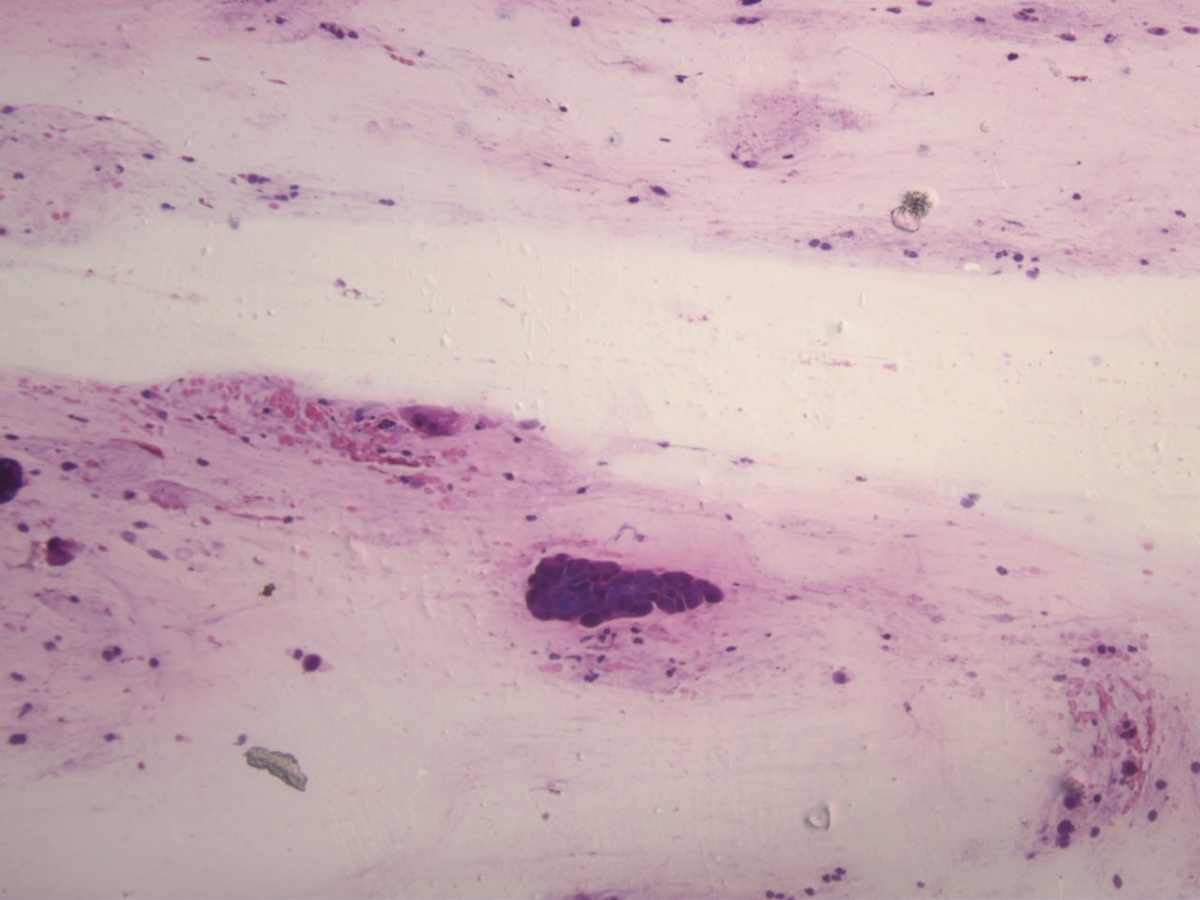

HSIL (носитель ВПЧ 16/18 тип) Жен. 28 лет

Традиционный цервикальный препарат.